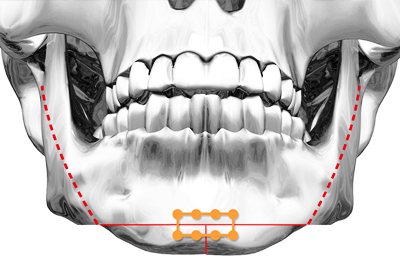

CASE 03 교근축소술

CASE 03 교근축소술사각턱 증상과 함께

앞턱이 뭉툭한 케이스인 경우

케이스에 따라

피질제거술/교근축소술 병행 -

이중턱, 이차각

가능성을 최소화한

매끈한 얼굴라인 완성